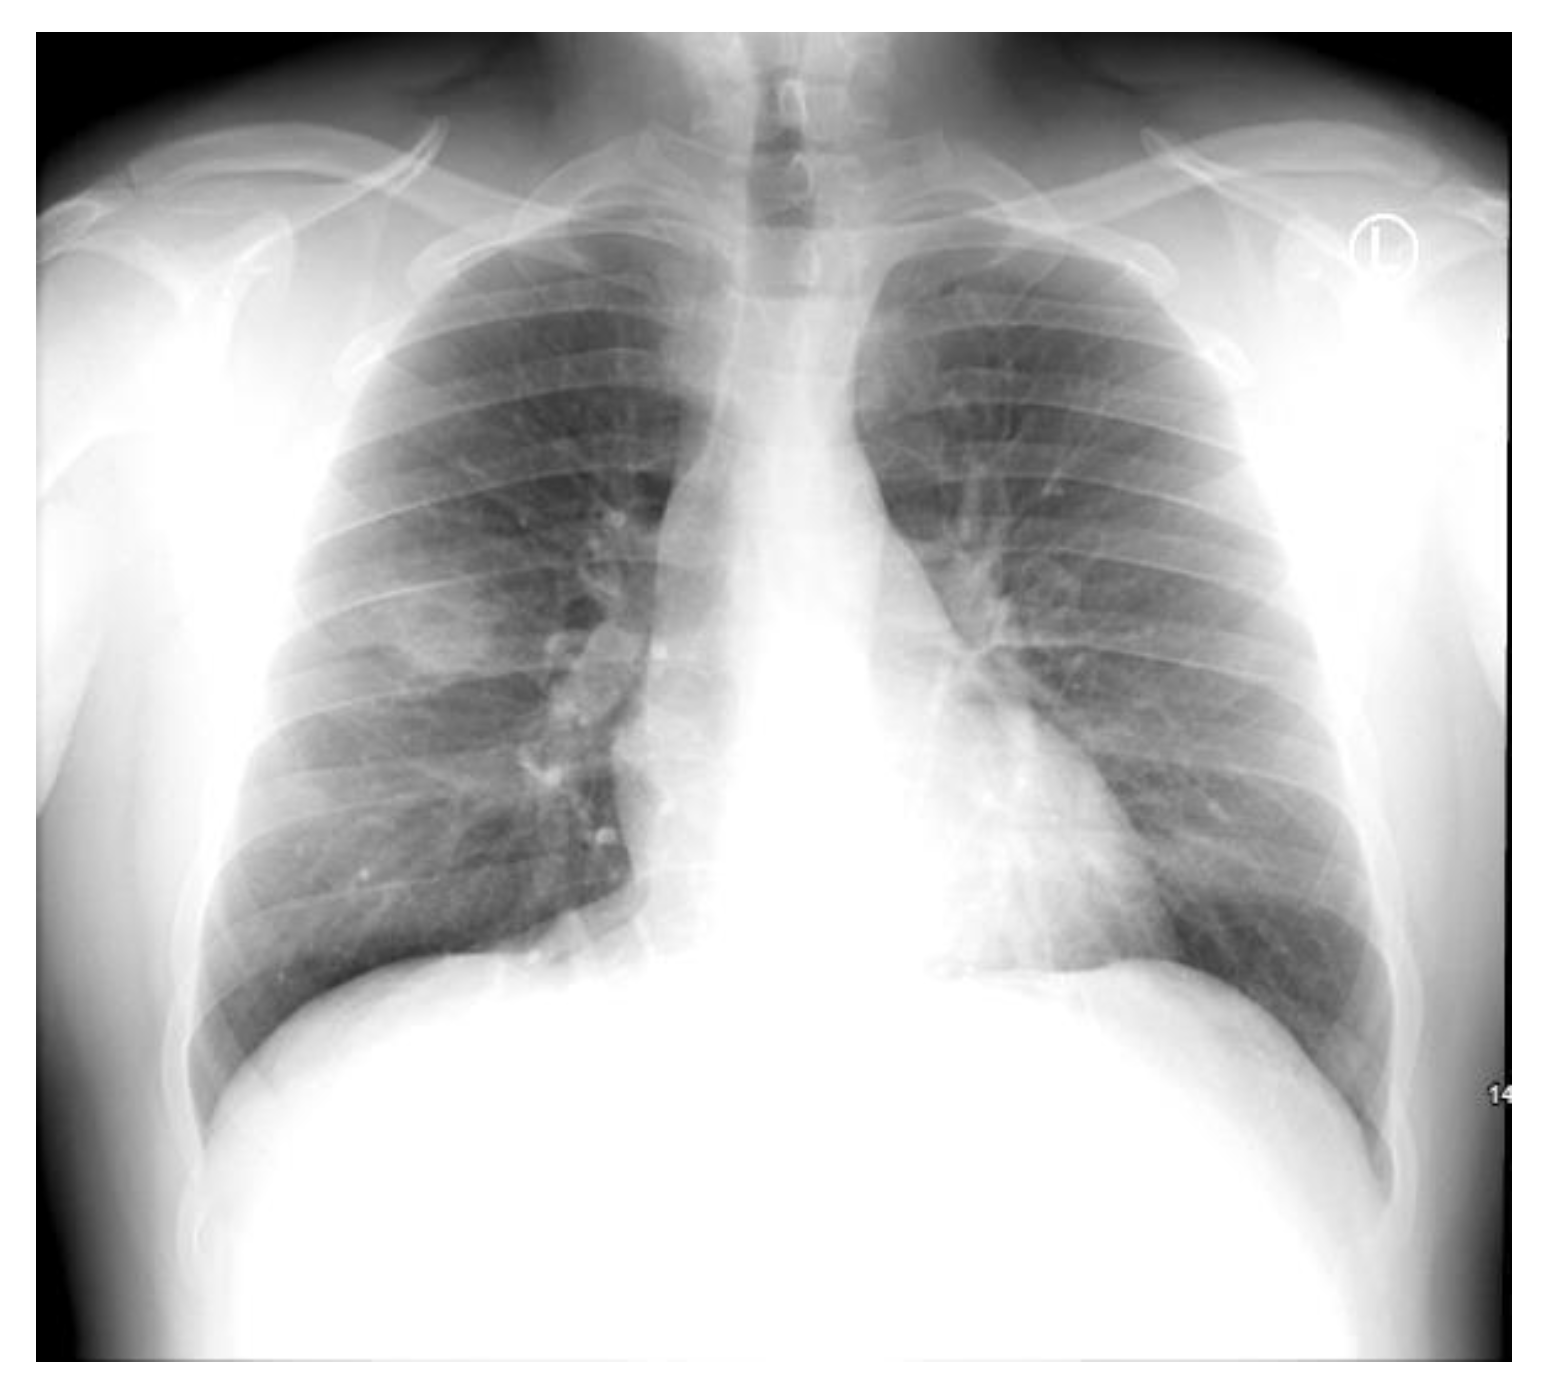

Chest X-ray showed a cavitating lesion in the right upper lobe (RUL), consistent with a cavitating pneumonia (Figure 1). He was empirically commenced on IV amoxicillin/clavulanate 1.2 g TDS and PO clarithromycin 500 mg BD for community-acquired pneumonia in accordance with local antibiotic guidelines.

Figure 1.

Admission chest X-ray demonstrating a right upper lobe cavitating pneumonia.